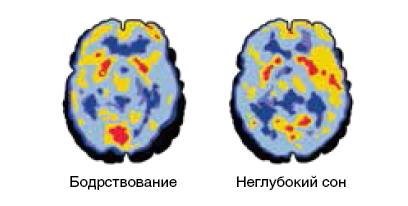

Из этого состояния он перешёл в сон, а во сне сознание, мягко говоря, не так активно, как в бодрствующем состоянии. Однако, когда дремлет сознание, мозг вовсе не спит, а, напротив, активно продолжает работать.

Именно во сне мозг доводит, так сказать, до ума – интегрирует и перераспределяет – интеллектуальные объекты, наши мысли и инсайты, появившиеся в нём во время бодрствования.

В этом, кстати, нетрудно убедиться, если сравнить активность бодрствующего мозга, с одной стороны, и мозга, находящего в знаменитой REM-фазе сна, зафиксированную с помощью позитронноэмиссионной томографии (ПЭТ), с другой9. Взгляните на рис. 5.

Рис. 5. Активность мозга человека, находящегося в разных состояниях сна и бодрствования, зафиксированная с помощью ПЭТ.